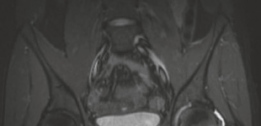

Magnetic resonance imaging (MRI) is highly sensitive for detecting the profound bone marrow edema and adjacent soft tissue inflammation characteristic of osteoid osteomas. While MRI may obscure the nidus itself due to the overwhelming edema signal, it is invaluable for assessing the extent of reactive synovitis, evaluating the integrity of the articular cartilage, and identifying concurrent labral pathology.